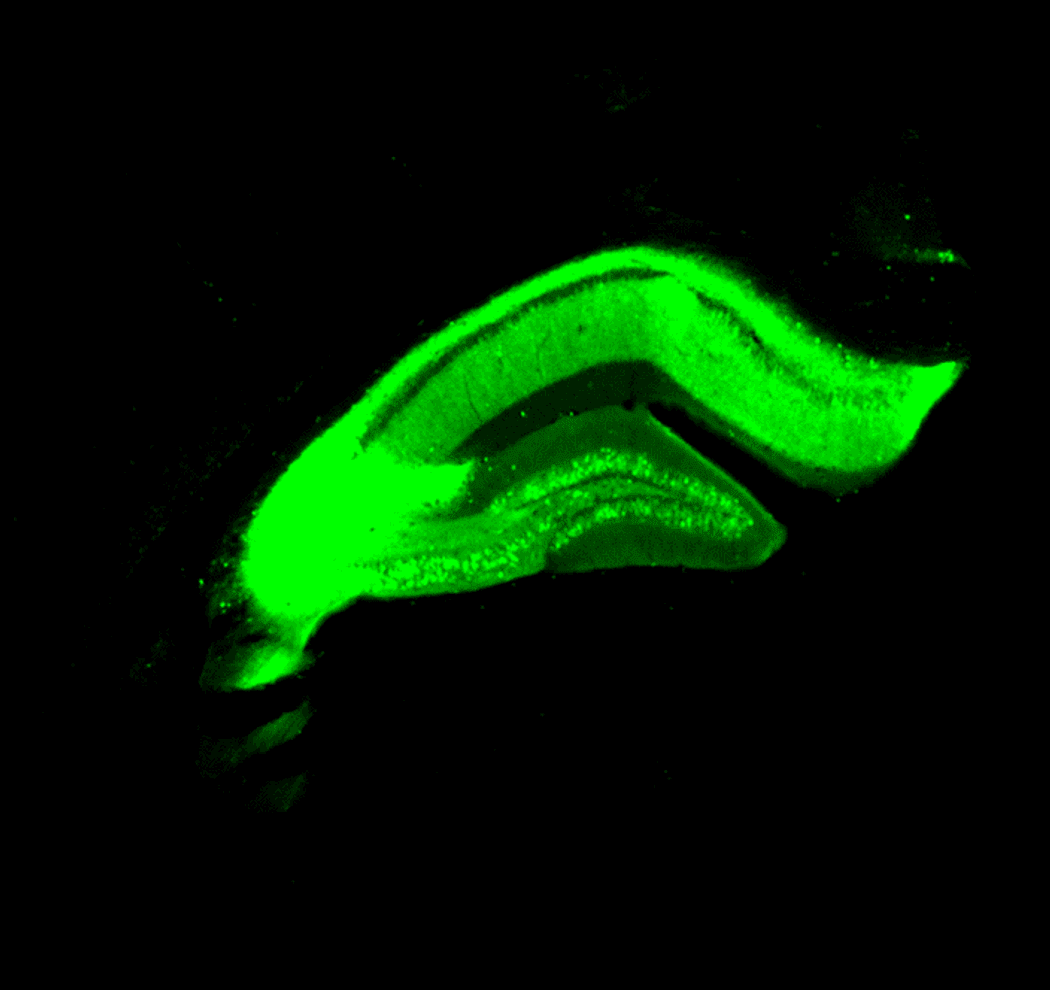

In a collaboration between Ronald Crystal and Steven Paul’s labs, the APOE2 gene was delivered into the hippocampus of APOE knockout mice.

Credit: Mayur Parmar and Lingzhi Zhao